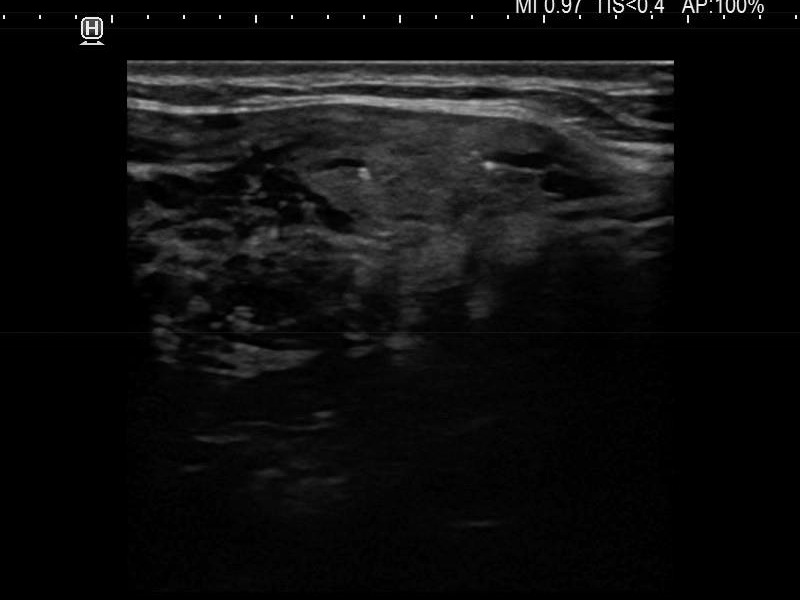

Intranodular hyperechogenic figures - case 694 (ultrasonographic picture 8)

Left lobe, another longitudinal view. The lower echogenic granule (right in the image) is located dorsal to a cystic area.